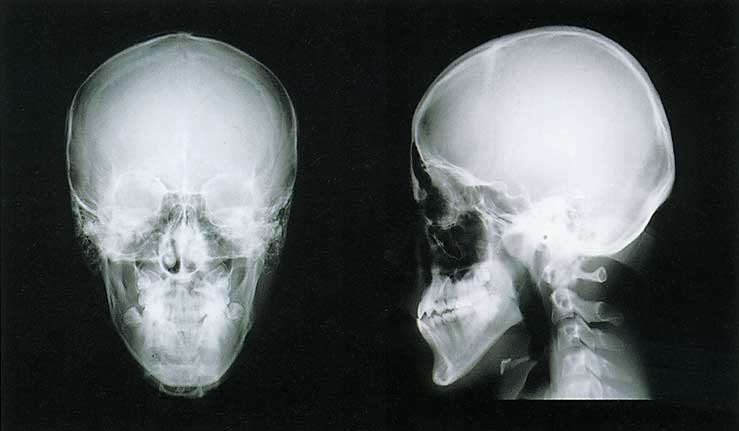

現代高校生男子

現代高校生男子(とくに細面)

(資料提供・新潟大学歯科矯正学教室)